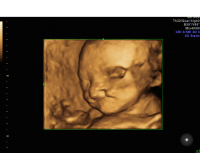

Cleft lip 3D profile

Cleft lip 3D